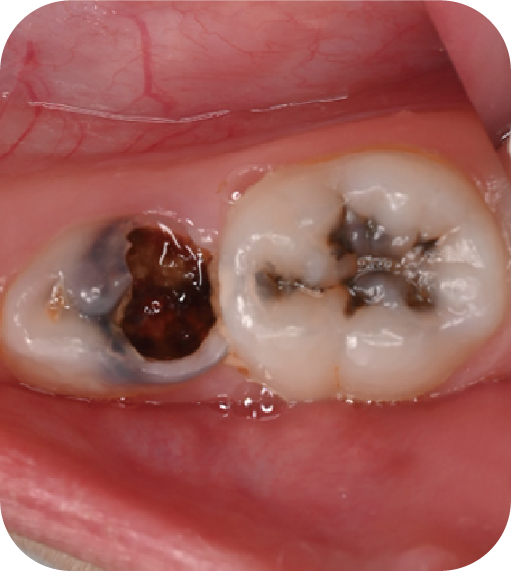

為什么要做窩溝封閉?

后磨牙,也就是大牙咬合面上凹凸不平的裂隙,這就是“窩溝”。窩溝有很多形狀,有的是狹長(zhǎng)的裂隙形狀,還有的在牙齒深處又會(huì)分成幾條小溝。這些地方用牙刷很難深入清潔,于是就成了衛(wèi)生死角,細(xì)菌特別喜歡在里面生存,不斷產(chǎn)酸腐蝕牙齒,蛀牙就這樣產(chǎn)生了。如果我們用窩溝封閉把這些衛(wèi)生死角封起來,那既可以杜絕食物和細(xì)菌進(jìn)入窩溝內(nèi),也可以讓窩溝處的清潔變得更簡(jiǎn)單,這就是做窩溝封閉的目的。同時(shí)它也是世界衛(wèi)生組織、國(guó)家衛(wèi)健委都推薦的防齲方法。